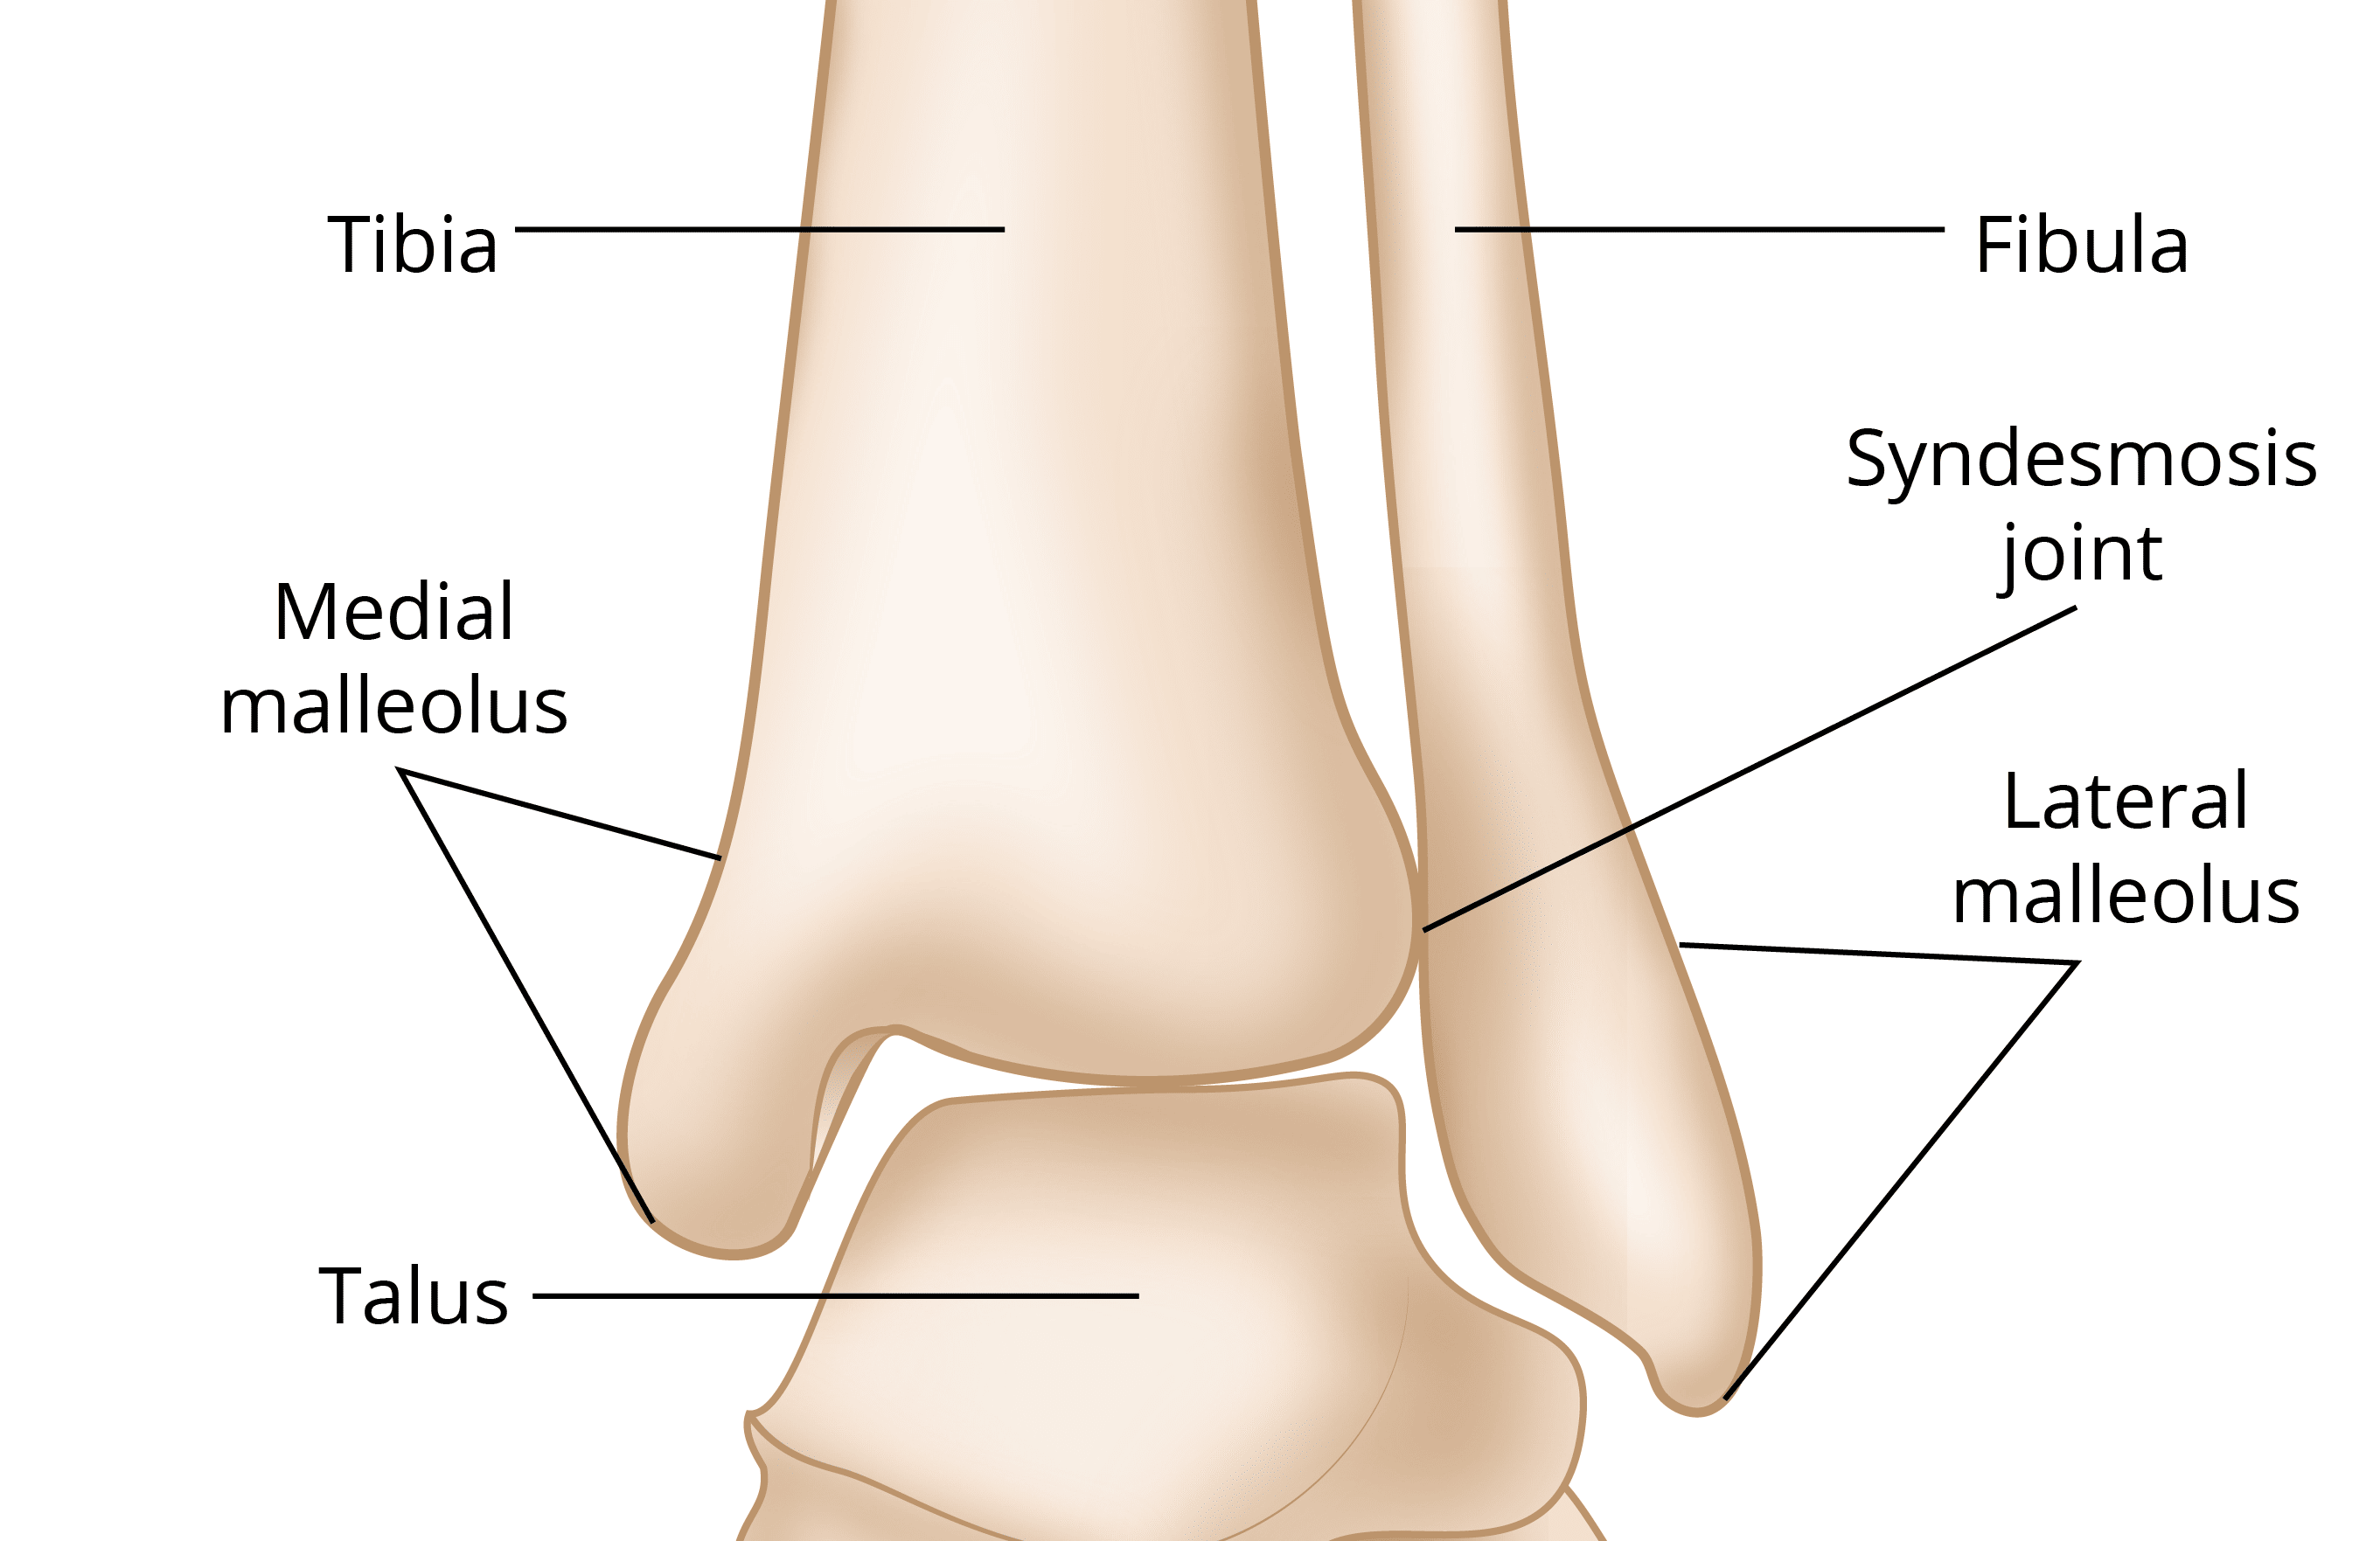

what are the joints of the ankle complex?

distal tibiofibular joint

talocrural joint

subtalar joint

what type of joint is the tibiofibular joint?

syndesmosis joint

what are the ligaments of the tibiofibular joint?

anterior inferior tibiofibular (AITF)

posterior inferior tibiofibular (PITF)

what is the talocrural joint?

known as the ankle joint

what can the talocrural joint also be classified as?

mortise joint

tibiotalar joint

fibulotalar joint